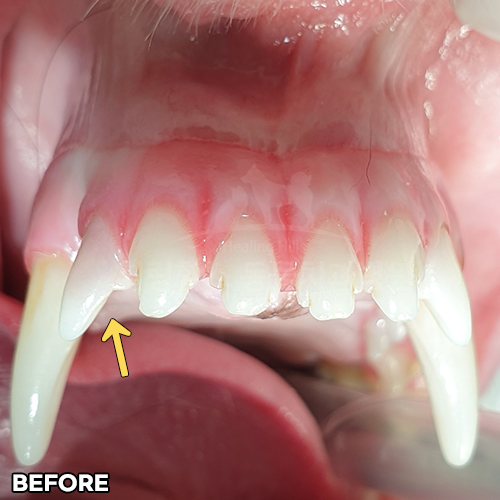

1.1kg 극초소형견 강아지치주염으로 입냄새나고 잇몸에 피가 나서 치료받았어요 & 매복치발치 - 동물치과 힐링힐스 -